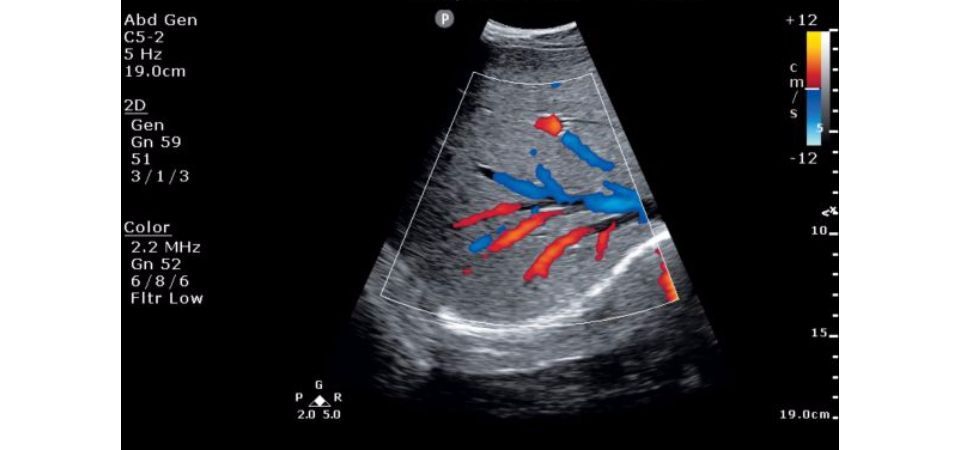

• FloVue: Усовершенствованная парадигма визуализации кровотока. Фирменные технологии Philips обработки сигнала от кровотока обеспечивают высокоразрешенное изображение кровотока как в крупных, так и в микрососудах.

• Функция FloVue: Усовершенствованный подход к визуализации кровотока, использующий технологии обработки сигнала от потока, позволяет получать изображения кровотока с высоким разрешением в крупных и мелких сосудах.

FloVue:

Да

• Высокочувствительный допплер (визуализация микрососудов) - Да

• Цветной допплер (CD) - Да

FloVue, QLAB IMT